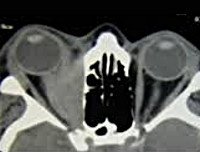

• КТ головного мозга и орбит. Пораженная мышца веретенообразно утолщена. При осмотре глазницы в аксиальной проекции обнаруживается экзофтальм средней степени выраженности. Объём мышечной ткани и века увеличен. Ретробульбарное пространство не изменено.